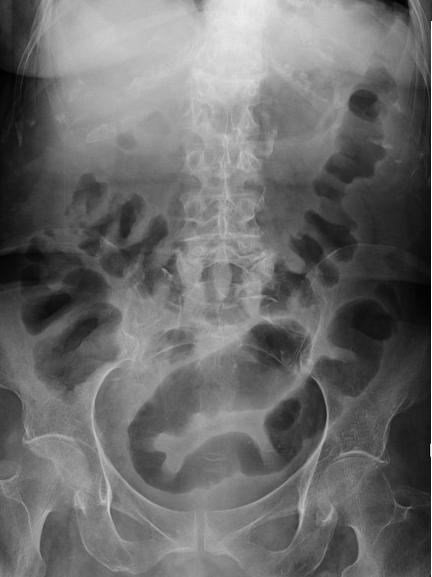

Aspect TDM une colite ischemique est :

lesion segmentaire regionale , Epaissisement de la paroi du

colon en symetrique ou lobulaire , stricture irreguliaire

segmentaire du colon ., oedeme de la muqueuse en forme signe

de cible " target sign ", presente de gas intramurale ou a

la veine porte , thrombus de artere ou veine mesenterique

superieur .

Epaissisement

stenosante de la paroi du colon descendante , Image

radiologique TDM en coupe coronale d'une colite

ischemique |

Epaissisement de la paroi du colon

d'une colite ischemique du colon transverse . Image

radiologique TDM en coupe axiale . |